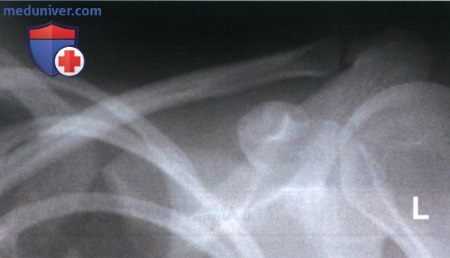

Рекомендации по анализу рентгенограммы (рис. 1):

РИСУНОК 1 Рентгенограмма ключицы в аксиальной ПЗ проекции, демонстрирующая ее правильное положение. РИСУНОК A Рентгенограмма ключицы в ПЗ проекции. Пациент повернут в противоположную сторону от исследуемой ключицы. РИСУНОК B Рентгенограмма ключицы в ПЗ проекции. Пациент повернут в сторону исследуемой ключицы.

• Медиальный конец ключицы находится вблизи латерального края позвоночного столба (рис. А и B)

• Верхний угол лопатки визуализируется на 1,25 см ниже ключицы

• Медиальный конец ключицы накладывается на первое, второе и третье ребра

• Средняя и латеральная трети ключицы визуализируются выше акромиального отростка, ключица изогнута вверх (рис. 3 и 4)

• Середина ключицы находится в центре экспозиционного поля

• В экспозиционное поле входят ключица и акромиальный отросток

РИСУНОК 3 Рентгенограмма ключицы в ПЗ проекции: перелом. РИСУНОК 4 Рентгенограмма ключицы в аксиальной ПЗ проекции: перелом.

б) Наклон ЦЛ. При рентгенографии ключицы в аксиальной ПЗ проекции краниальный наклон ЦЛ на 15-30° позволяет спроецировать большую часть ключицы выше грудной клетки и оценить степень смещения отломков при наличии перелома. Несмотря на то, что степень наклона в разных медицинских учреждениях может различаться, на всех рентгенограммах ключица будет сдвинута вверх.

Чем больше угол, тем выше будет проецироваться ключица. Поскольку в 80% случаев перелом ключицы происходит в ее средней трети и в 1 5% случаев — в ее латеральной трети, целесообразно ЦЛ наклонять так, чтобы латеральная и средняя трети ключицы визуализировались выше грудной клетки и лопатки. Сравните рентгенограммы на рис 3 и 4 (см. выше) и обратите внимание, как увеличение краниального наклона ЦЛ позволяет спроецировать латеральную и среднюю трети ключицы выше лопатки. На обеих рентгенограммах перелом ключицы очевиден, однако без рентгенограммы в аксиальной ПЗ проекции перелом ключицы без смещения на фоне лопатки можно не заметить.

Пример анализа рентгенограммы ключицы в аксиальной ПЗ проекции

а) Анализ. Медиальный конец ключицы накладывается на третье ребро. Латеральный конец ключицы визуализируется не выше, а на уровне акромиального отростка. ЦЛ был наклонен недостаточно.